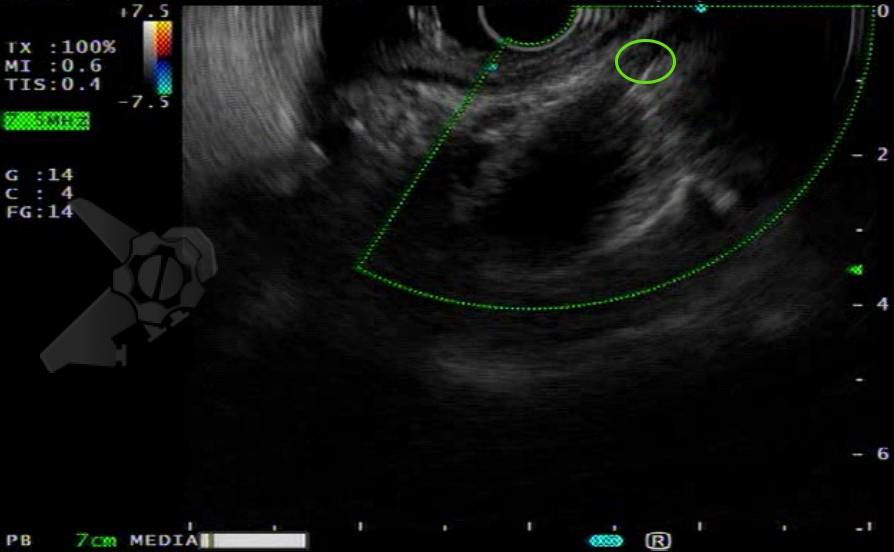

Após preparo colônico com manitol e a realização de uma nova radiografia, que não apontou qualquer mudança na posição inicial da prótese dentária desde a admissão, o paciente foi submetido a colonoscopia. Até a intubação cecal o corpo estranho não foi encontrado, com presença de doença diverticular no hemicólon esquerdo (foto 2 e 3).